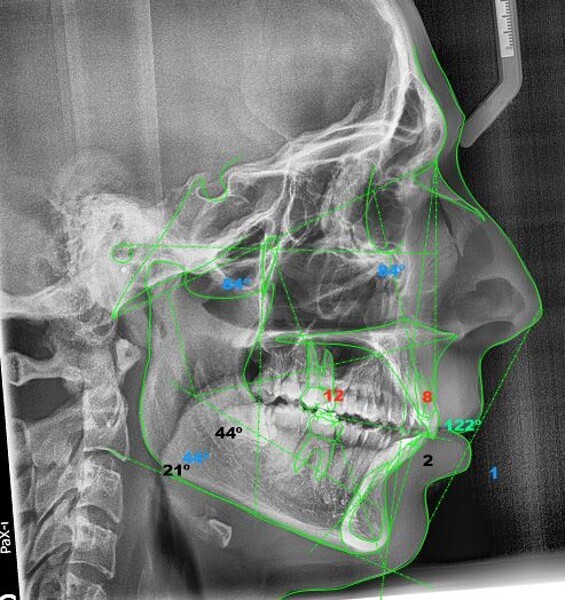

In the radiographic analysis, the dental panoramic tomogram revealed that the two mandibular third molars were unerupted and horizontalised in the mandible. Nothing else relevant was observed in the radiograph (Fig. 3). A cephalometric radiograph was used to perform the cephalometric analysis according to Steiner,6 Ricketts7, 8 and McNamara9 (NemoCeph Studio, Nemotec Fig. 4).

In the Steiner analysis, the SNB angle of 74° suggested mandibular retrusion. Likewise, the ANB angle of 7° indicated Class II, which was also confirmed by Wits analysis (8.3 mm). The results indicated a protrusion of the maxillary incisors and a decreased inter-incisal angle of 118°, which suggested protrusion of the maxillary and mandibular incisors (Fig. 5).

In the Ricketts analysis, a dolichofacial pattern, that is, a facial axis of 84°, was diagnosed. The analysis also confirmed the protrusion of the incisors (Fig. 6).

The McNamara analysis revealed that the size of the mandible that would correspond to the dimensions of the maxilla (91.0 mm) would be between 114.0 mm and 117.0 mm and not the current size of 111.9 mm,9 indicating that the mandible was smaller than it should have been. However, the maxillomandibular difference was 20.9 mm, indicating a Class II skeletal pattern (Fig. 7). From the aforementioned information, we determined a Class II skeletal pattern and dental relationship with retrusion of the lower jaw and an increased overjet and overbite.